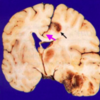

What is the structure? [1]

What has been stained brown using immunohistochemistry? [1]

A Lewy body (stained brown) in a brain cell of the substantia nigra in Parkinson’s disease. The brown colour is positive immunohistochemistry staining for alpha-synuclein.